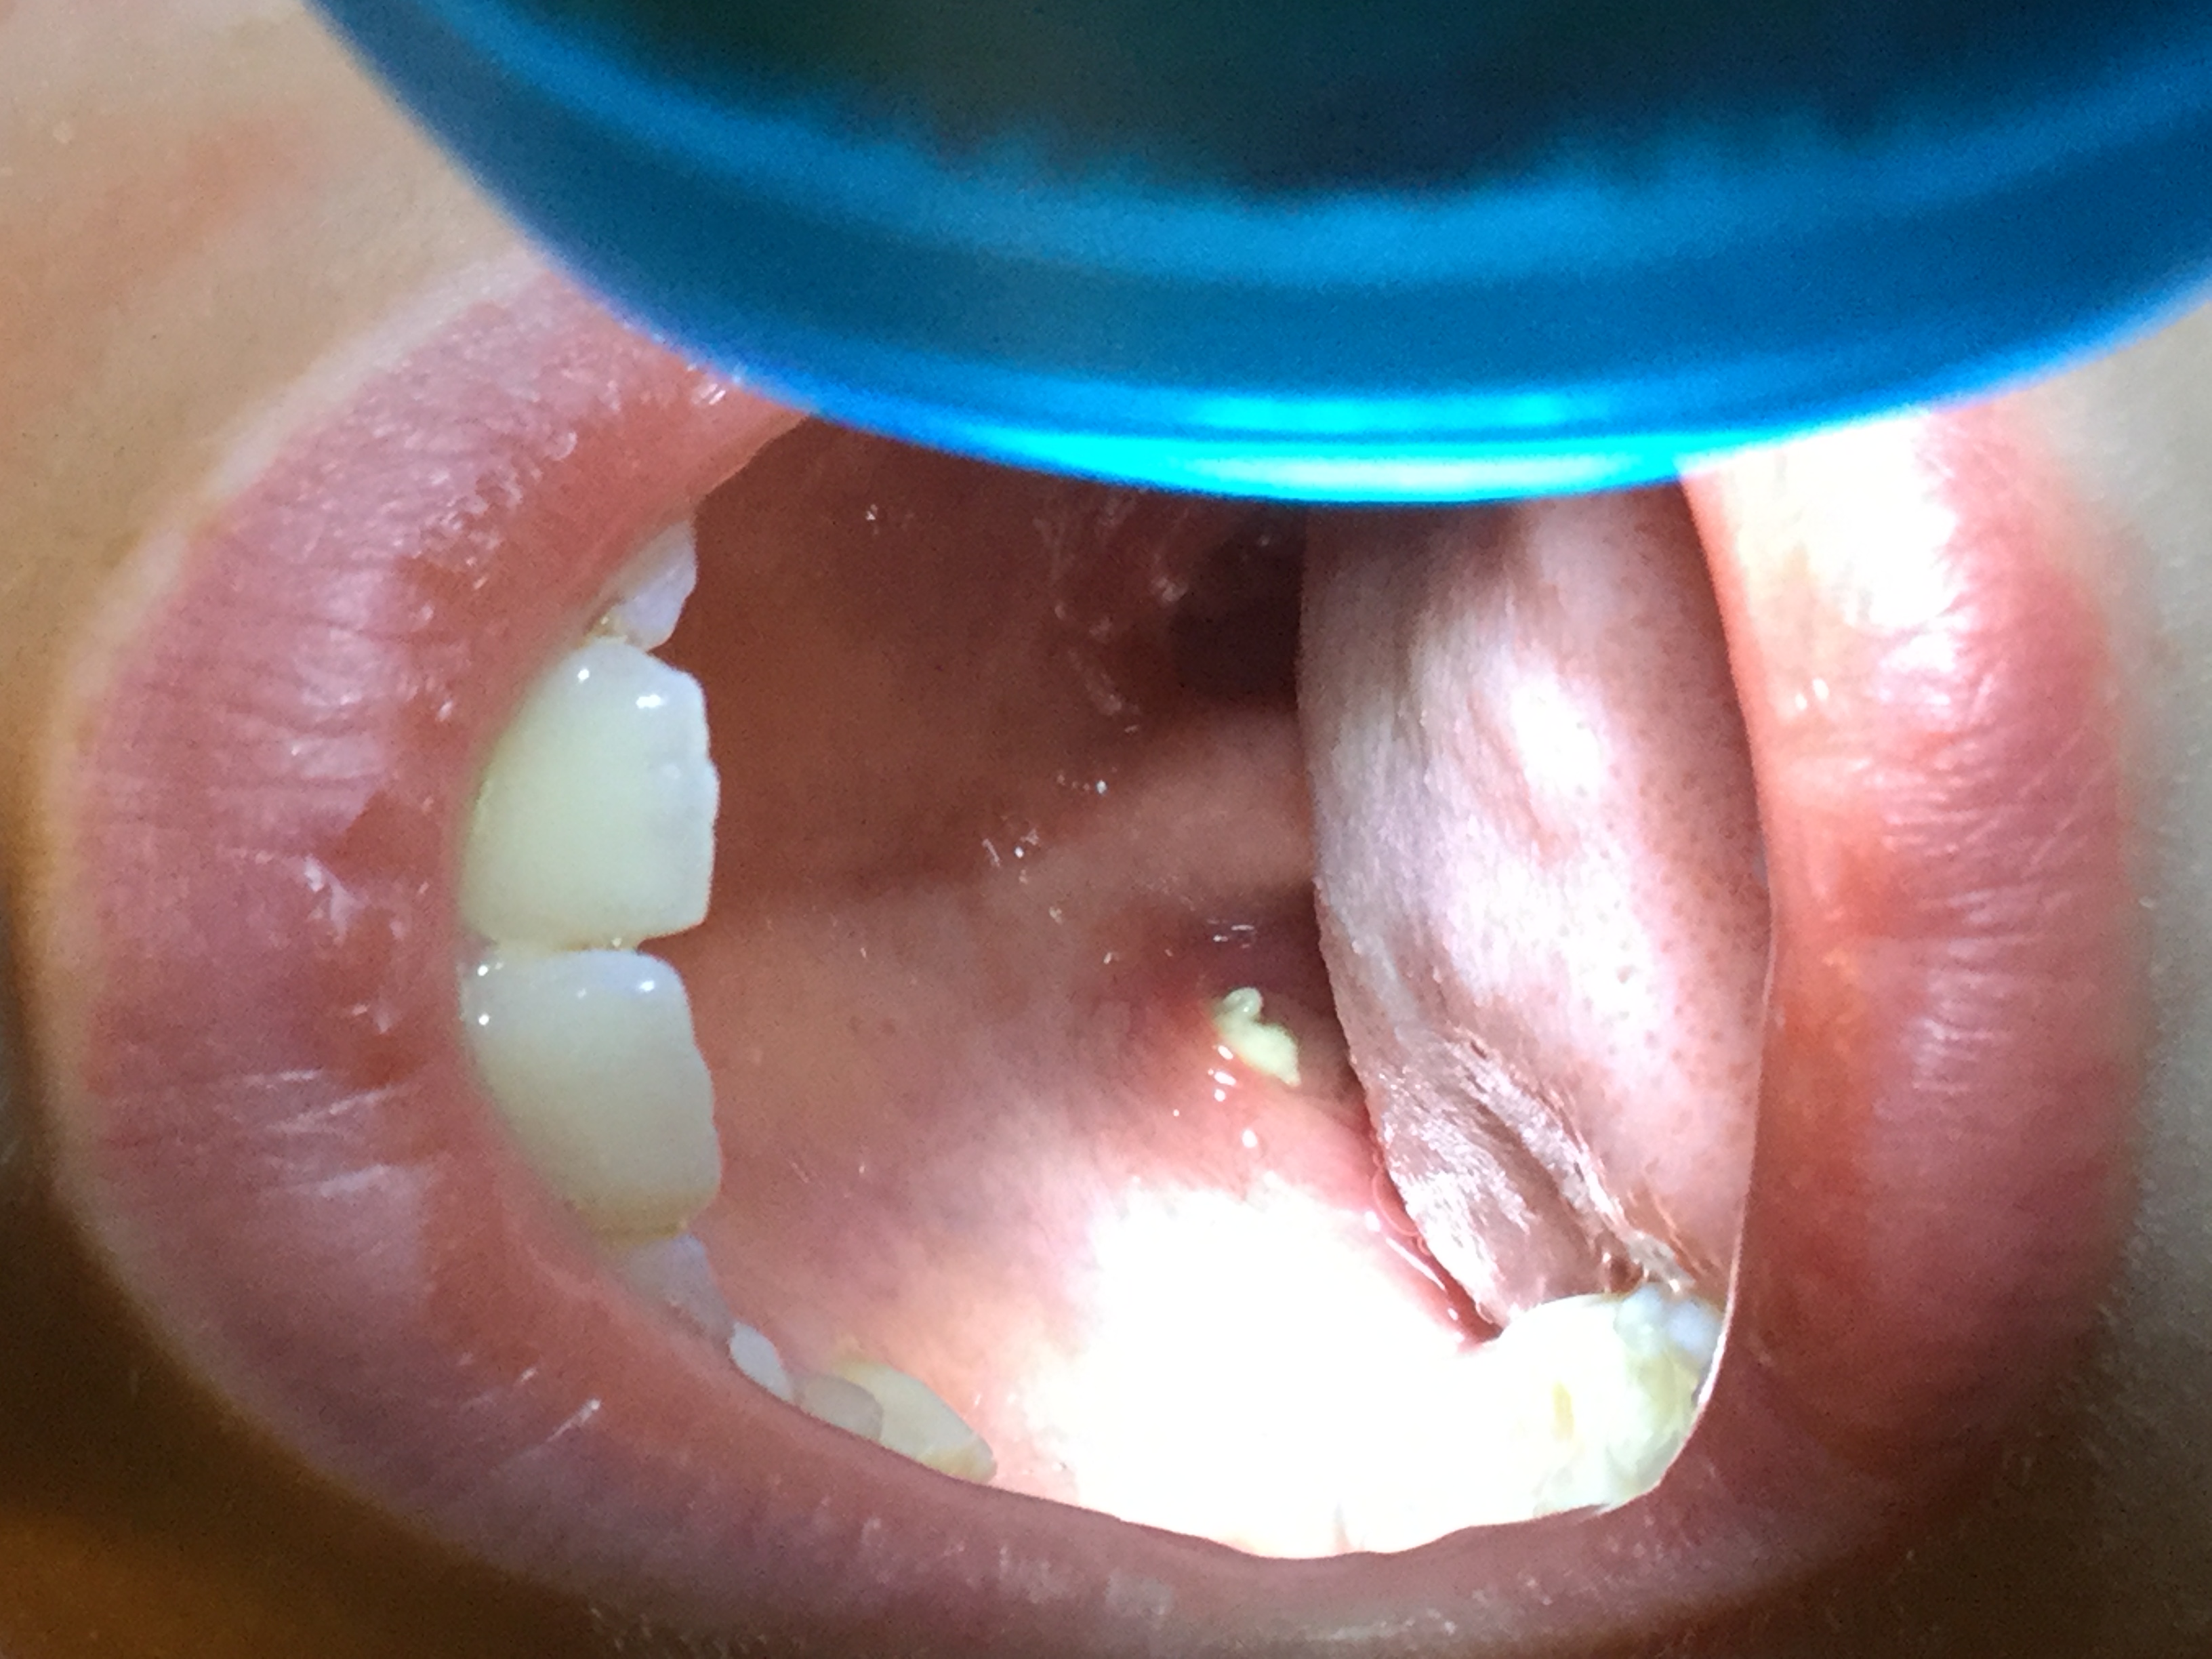

http://home.wanadoo.nl/erdgi/gehemeltegaatjes.jpg

kan niet echt scherp inzoomen en juist belichten tegelijk :oops:

en niet op het gebit letten ;) want daar gaat de vraag niet over :smt003

t zit niet diep in mn mond, een cm of 2 voor de 'amandel', net over de

grens van het zachte stuk.. als ik ziek word worden ze vrij groot en

geirriteerd en kunnen dan vreselijk veel pijn doen..

Qua plaatsing zouden dit toch echt de fovae palatina moeten zijn, maar ze zijn inderdaad behoorlijk groot.

(Als je nu een lijntje trekt vanachter de laatste kiezen door de fovae dan geeft dat ongeveer de scheiding van het harde naar het zachte gehemelte aan, zoals Erdgi ook al zelf zegt)

Laat, wanneer je bij de tandarts komt, even controleren of er echt lucht via deze gaatjes via de mond in de neusholte komt (of vice versa). Als dit echt zo is, kan het zijn dat de sutura palatina mediana(het gehemelte bestaat uit een linker en een rechter deel welke aan elkaar moeten groeien) niet gesloten is en tevens de bekleding van de neusbijholte niet intact is gebleven, waardoor er een open verbinding is ontstaan. De kans dat dit zo is is qua percentage wel iets dat zich een eindje achter de komma bevindt, maar echt onmogelijk is het niet.

Verder is het wel zo dat bij openingen van deze grote dit wel een retentieplek is voor voedselrestjes en bacterieen die ook voor irritatie kunnen zorgen.